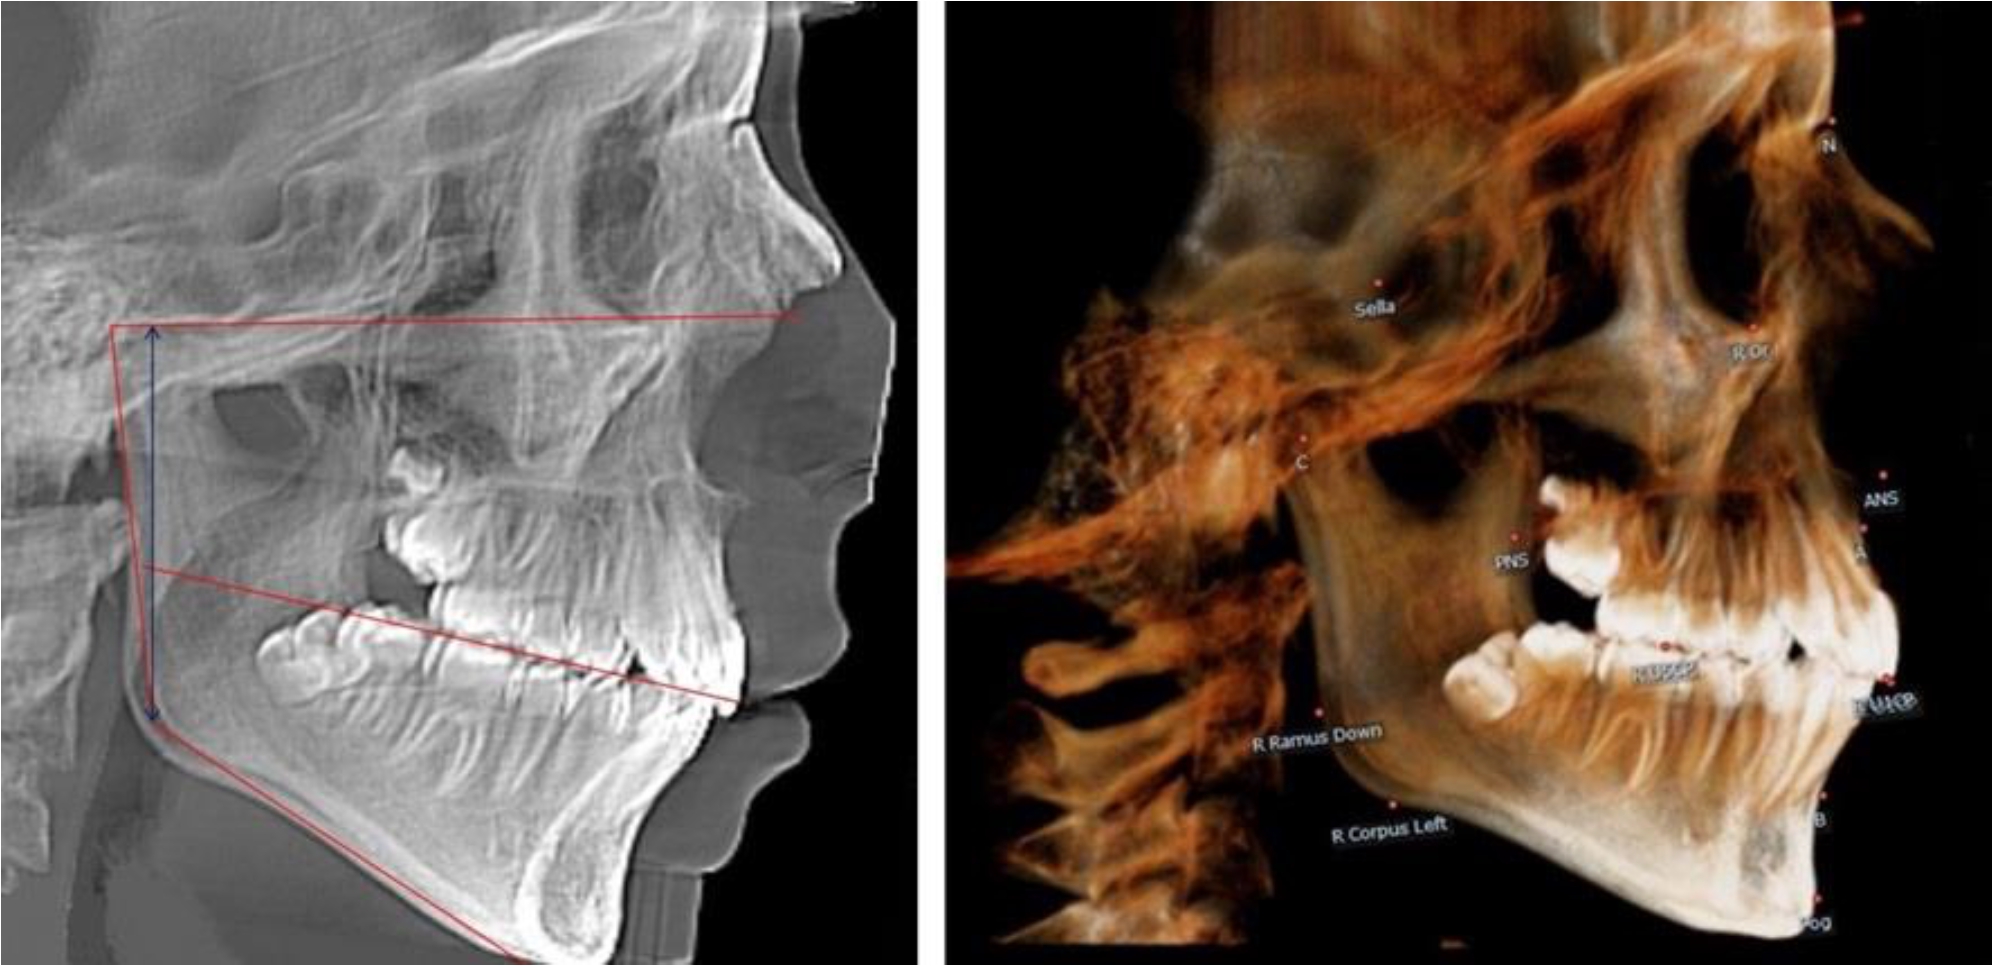

В 4-й группе были проанализированы 12 комплектов рентгенограмм, что составило (11,32 ± 3,08) % от общего числа. На всех рентгенограммах произошла полная смена всех молочных зубов постоянными. Окклюзионная линия делила ветвь на два отдела (рис. 4).

Рис. 4. ТРГ пациента после смены всех молочных резцов

Высота ветви у детей 4-й группы составляла (54,27 ± 2,59) мм, что было достоверно больше, чем у детей 1-й группы (р ˂ 0,05). При этом высота верхней окклюзионно-суставной части была (32,51 ± 1,72) мм, а нижней – (21,76 ± 1,42) мм. Высота верхней части была больше нижней, что и определяло особенности соразмерности частей ветви нижней челюсти в анализируемый возрастной период.

Относительные показатели соразмерности частей ветви нижней челюсти показали, что отношение высоты верхней части ветви к нижней в среднем составляло 1,49 ± 0,12. Отношение общей высоты ветви к верхней ее части составляло 1,67 ± 0,14, а отношение общей высоты ветви к нижней ее части было 2,49 ± 0,15, что и определяло особенности соразмерности частей ветви нижней челюсти в анализируемый возрастной период.

В 5-й группе были проанализированы 14 комплектов рентгенограмм, что составило (13,21 ± 3,29) % от общего числа. На всех рентгенограммах отмечен очередной этап подъема высоты прикуса, обусловленный прорезыванием вторых постоянных моляров. Окклюзионная линия делила ветвь на два отдела (рис. 5).

Рис. 5. ТРГ и ОПТГ пациента после смены молочных зубов и прорезывания вторых постоянных моляров

Высота ветви у детей 5-й группы составляла (62,87 ± 3,62) мм, что было достоверно больше, чем у детей других групп (р ˂ 0,05). При этом высота верхней окклюзионно-суставной части была (40,23 ± 2,01) мм, а нижней – (22,64 ± 1,78) мм. Высота верхней части была вдвое больше нижней, что и определяло особенности соразмерности частей ветви нижней челюсти в анализируемый возрастной период.

Относительные показатели соразмерности частей ветви нижней челюсти показали, что отношение высоты верхней части ветви к нижней в среднем составляло 1,78 ± 0,18. Отношение общей высоты ветви к верхней ее части составляло 1,56 ± 0,12, а отношение общей высоты ветви к нижней ее части было 2,78 ± 0,14, что и определяло особенности соразмерности частей ветви нижней челюсти в анализируемый возрастной период.

Таким образом, прорезывание постоянных зубов и смена молочных зубов постоянными изменяло не только высоту ветви нижней челюсти, но и изменяло соотношение ее частей, разделенных условной линией, являющейся продолжением окклюзионной линии рентгенограммы. Наиболее вариабельной структурой ветви являлась верхняя ее часть с суставным отростком. Окклюзионно-альвеолярная часть коррелировала с высотой зубочелюстных сегментов нижней челюсти.